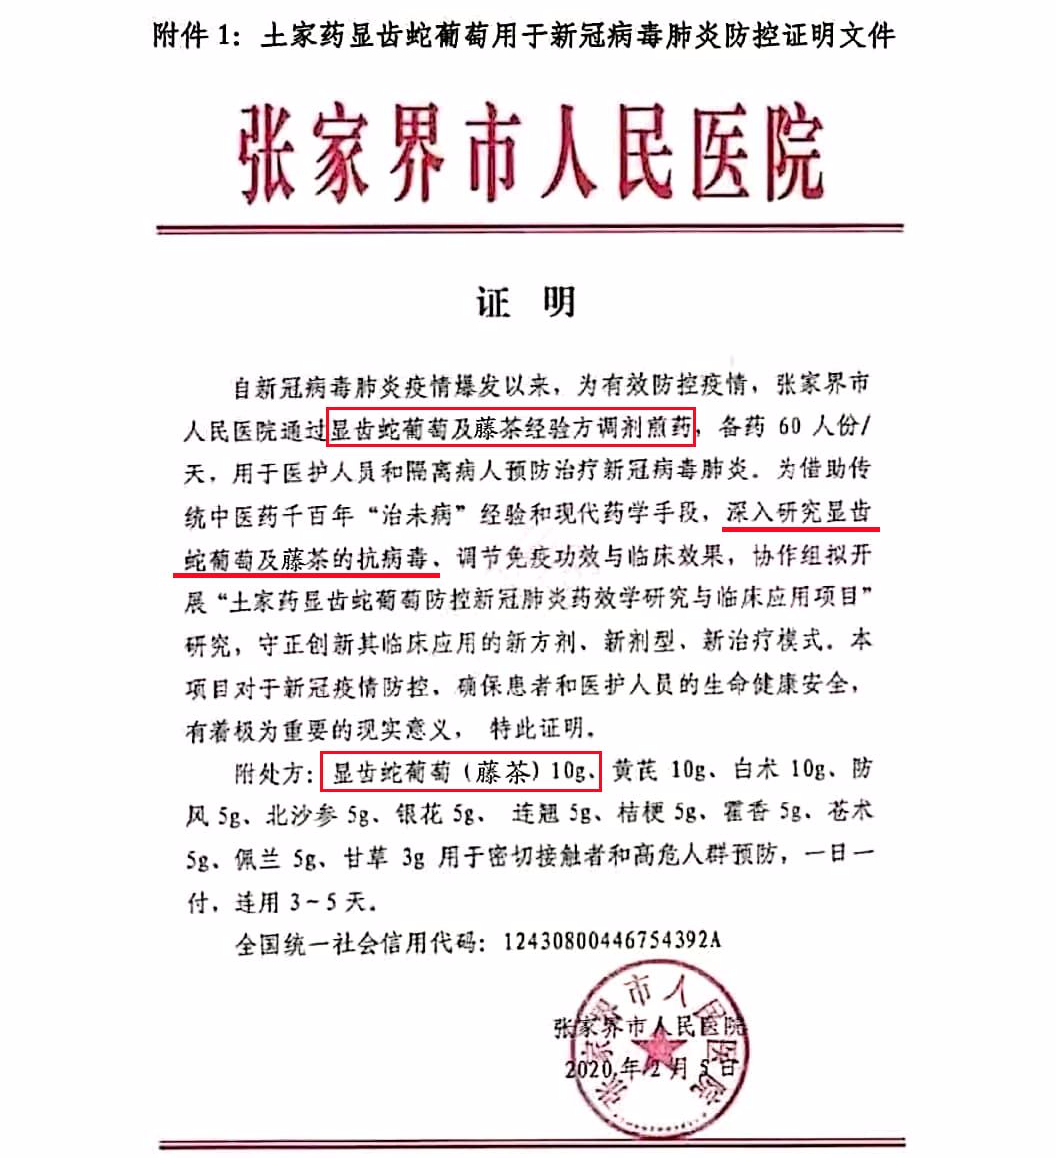

除此之外,土家莓茶对夜生活过度、烟酒过量、口干、舌燥、口苦乏力、神疲心烦的人,特别好!最令人惊讶的是——张家界人民医院把土家莓茶用于新肺炎病毒的防控!